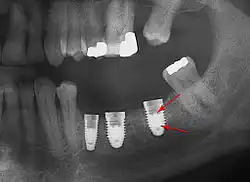

An implant is tested between 8 and 24 weeks to determine if it is integrated. There is significant variation in the criteria used to determine implant success, the most commonly cited criteria at the implant level are the absence of pain, mobility, infection, gingival bleeding, radiographic lucency or peri-implant bone loss greater than 1.5 mm.[92]

Dental implant success is related to operator skill,[93] quality and quantity of the bone available at the site,[2] and the patient's oral hygiene, but the most important factor is primary implant stability.[94] While there is significant variation in the rate that implants fail to integrate (due to individual risk factors), the approximate values are 1 to 6 percent[42]: 68 [75]